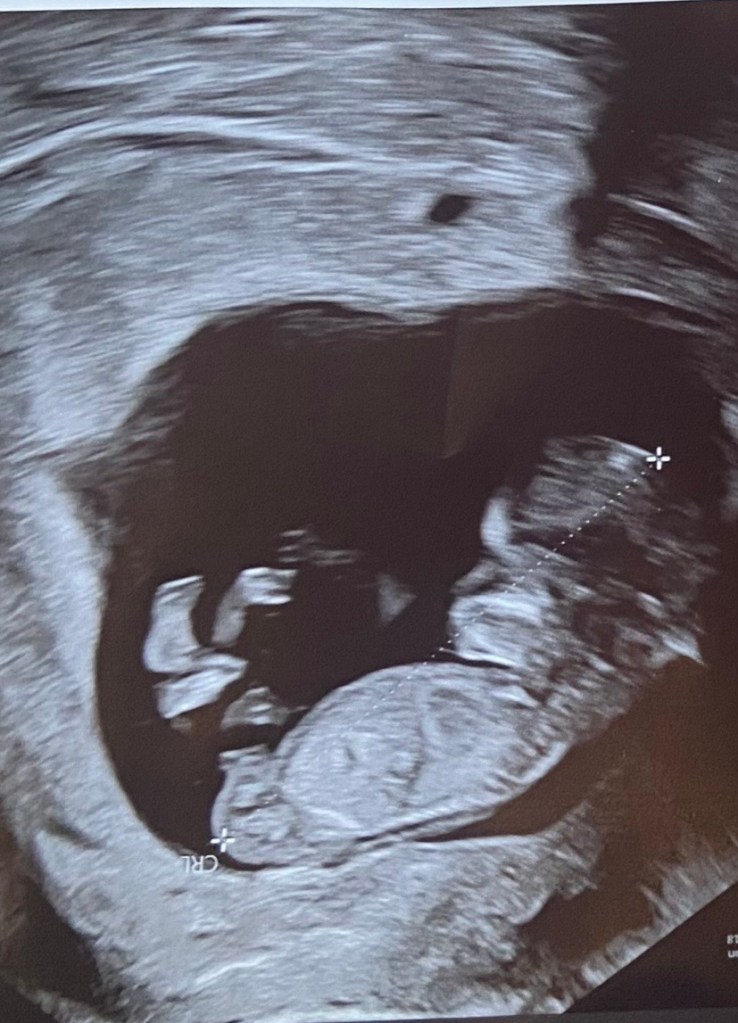

What truly set my OB apart is how much she genuinely cares. At our first ultrasound, she smiled when she saw our baby—and even after years of practicing, she still finds joy in those moments. She is hands-on, attentive, and present with her patients. I’m also a notoriously tough stick when it comes to blood draws, and she personally does it every single time. That level of care means everything to me.

Now that I’m in my second trimester, I’m feeling great—and finally enjoying this journey in a new way. I’m counting down the days until we meet our baby boy this June.